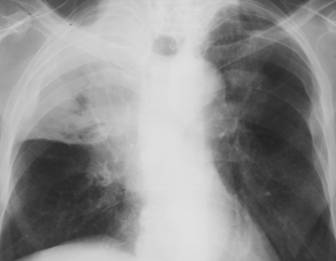

Fig. 13: Pneumonie pneumococica - opacitatiede intensitate medie, omogena cu bronhograma aerica, imprecis delimitata, de forma triunghiulara cu varful la hil.